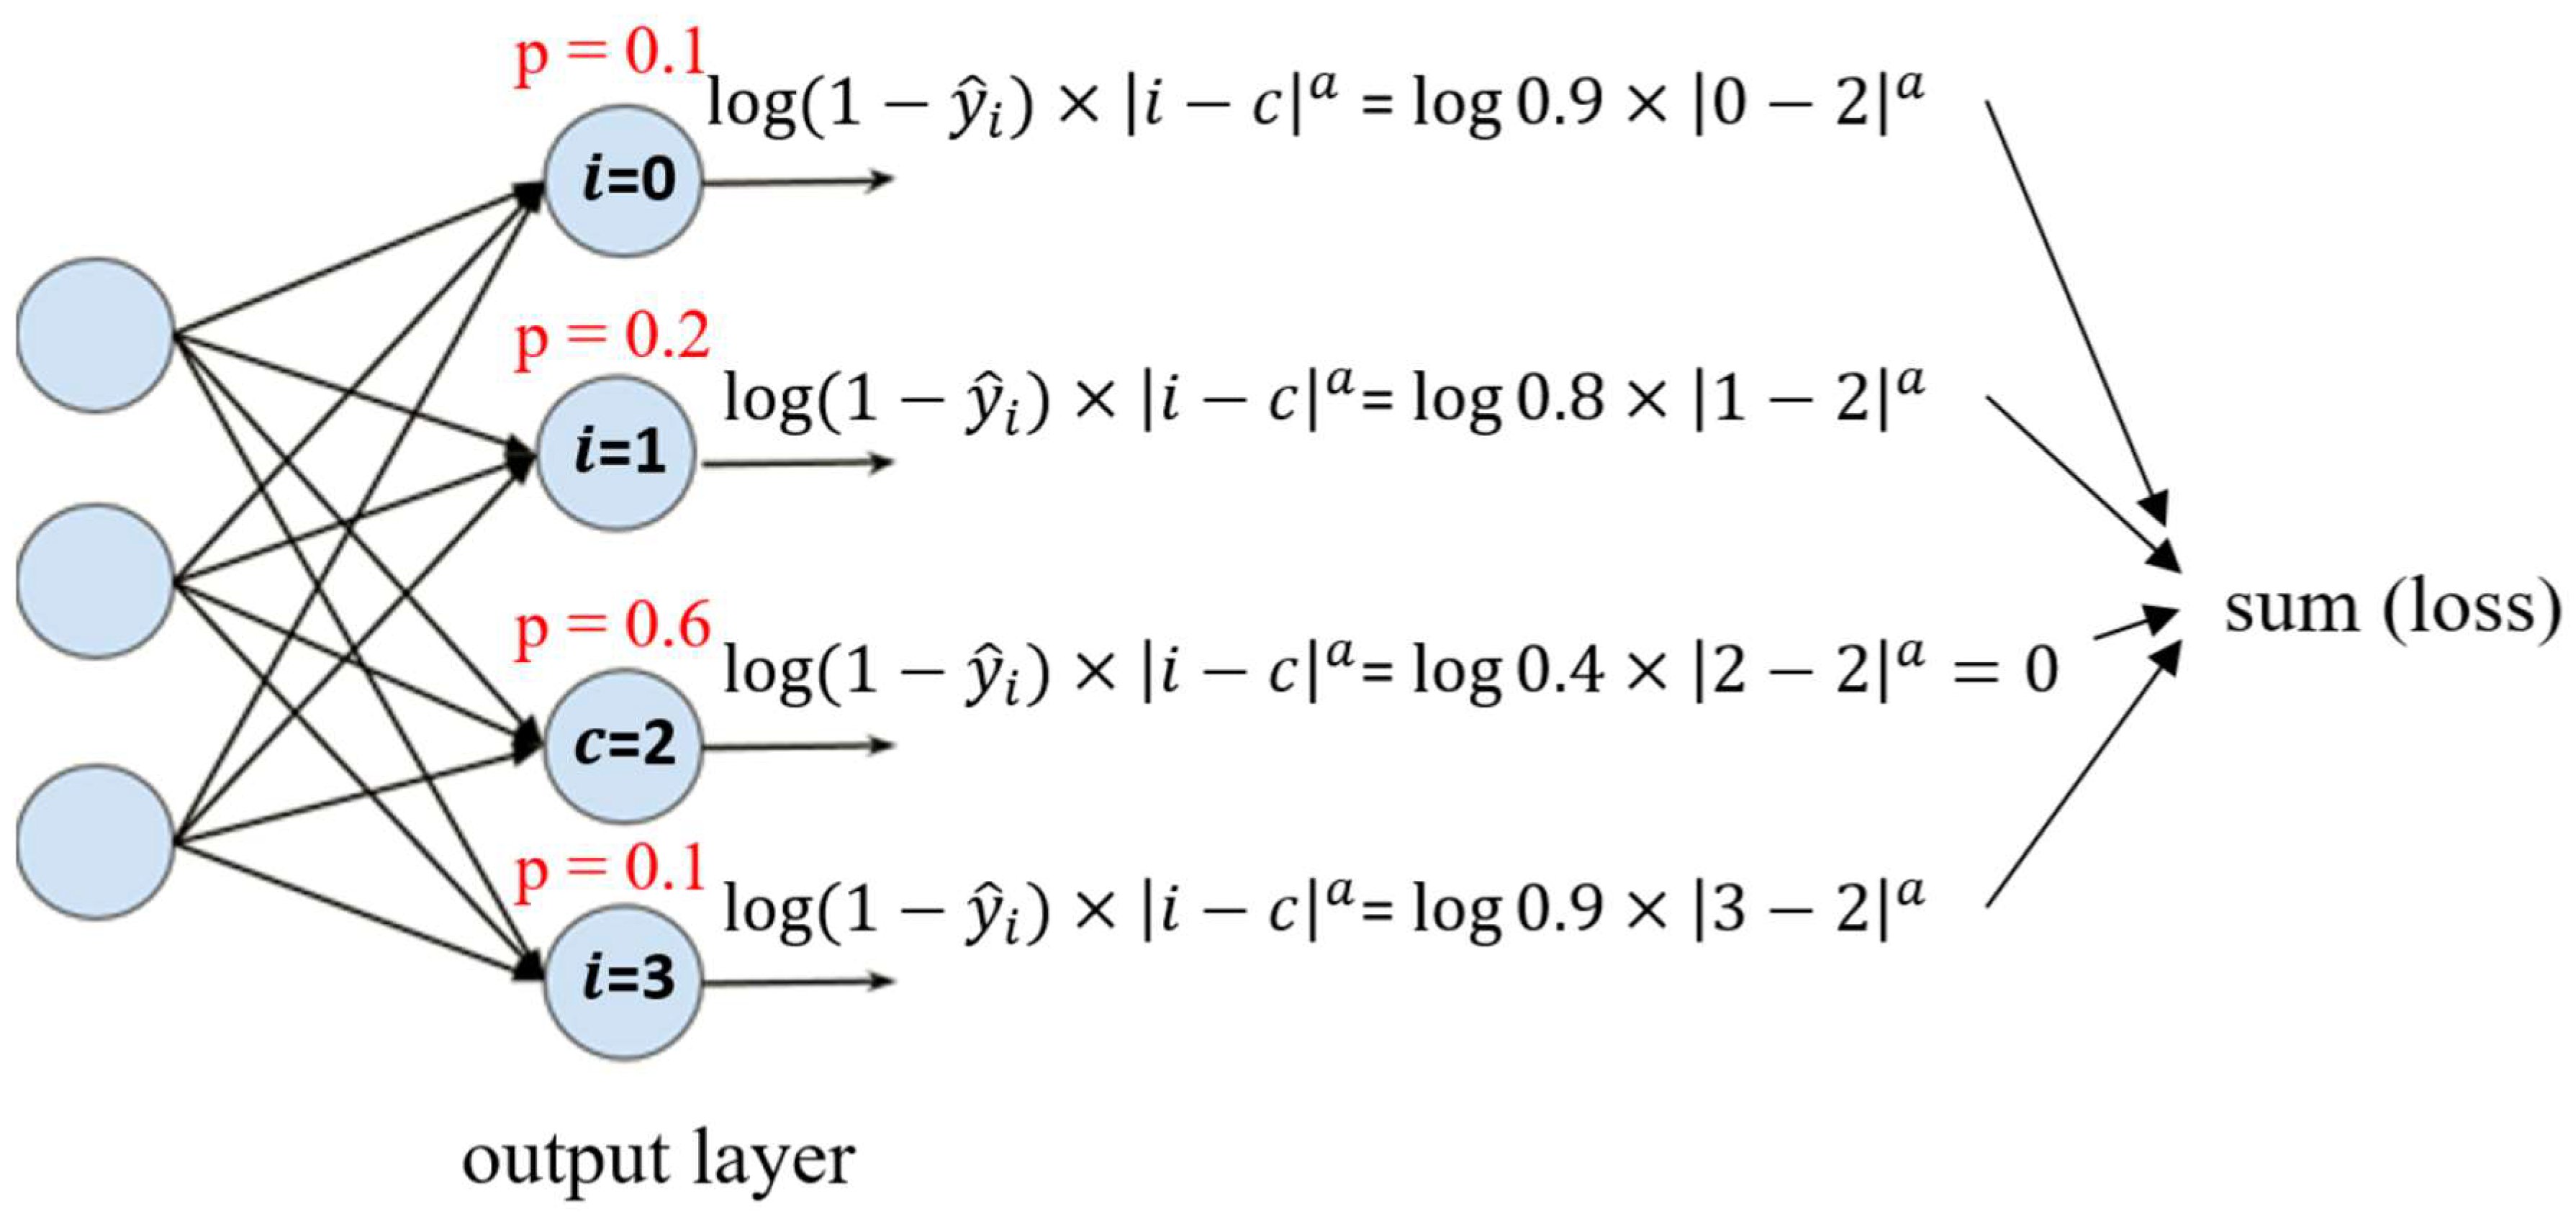

- The exponent a in the CDW-CE formula requires manual tuning of different values, making the process more time-consuming. Additionally, as a increases, the penalty intensity also increases, leading to higher loss values and longer training times.

- Through cross-validation training, larger a values result in less stable training, with a significant increase in standard deviation.

2.3. Other Neural Network-Based Methods for Ordinal Regression